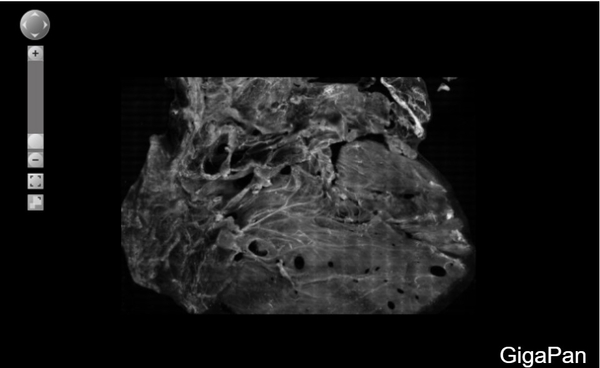

We have developed devices and contrast mechanisms that enable rapid, large-area 2D and 3D pseudo-histology in fresh biopsies and surgical resections using structured illumination microscopy (SIM) and selective-plane illumination microscopy (SPIM). In addition, with our collaborators we are developing novel computational strategies for automated cancer detection and analysis for grading and prognosis. We are committed to sustained efforts to clinically validate these technologies in realistic clinical scenarios towards clinical translation, and to accomplish this we employ a highly-collaborative team-based approach at the interface between engineering and medicine, working with engineers, clinicians, and scientists to develop and validate new technologies.